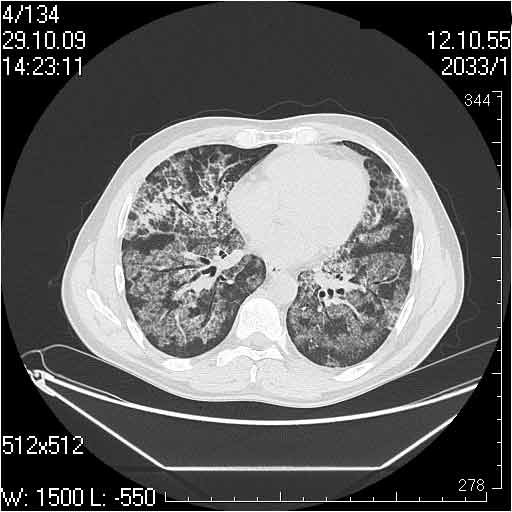

Случай №3

Женщина 51 год

Случай 3:смешанные изменения; подходят для интерстициальной пневмонии, тактика аналогична случаю 1.